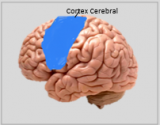

Die Neuroanatomie ist das Teilgebiet der Anatomie, das sich mit der Anatomie des Nervensystems befasst, d. h. mit der Struktur, Funktion und Organisation des Nervensystems. Das Nervensystem ist eines der komplexesten Systeme im menschlichen Körper und umfasst das Gehirn, das Rückenmark, die peripheren Nerven und die Nervenganglien. Die Neuroanatomie befasst sich damit, wie diese Strukturen miteinander verbunden sind, wie Signale zwischen den Nervenzellen übertragen werden und wie die verschiedenen Teile des Nervensystems zusammenarbeiten, um körperliche und kognitive Funktionen zu steuern. Neuroanatomen verwenden fortschrittliche bildgebende Verfahren wie Magnetresonanztomographie (MRT), Positronenemissionstomographie (PET) und Mikroskopie, um die Strukturen und Funktionen des Nervensystems sichtbar zu machen.